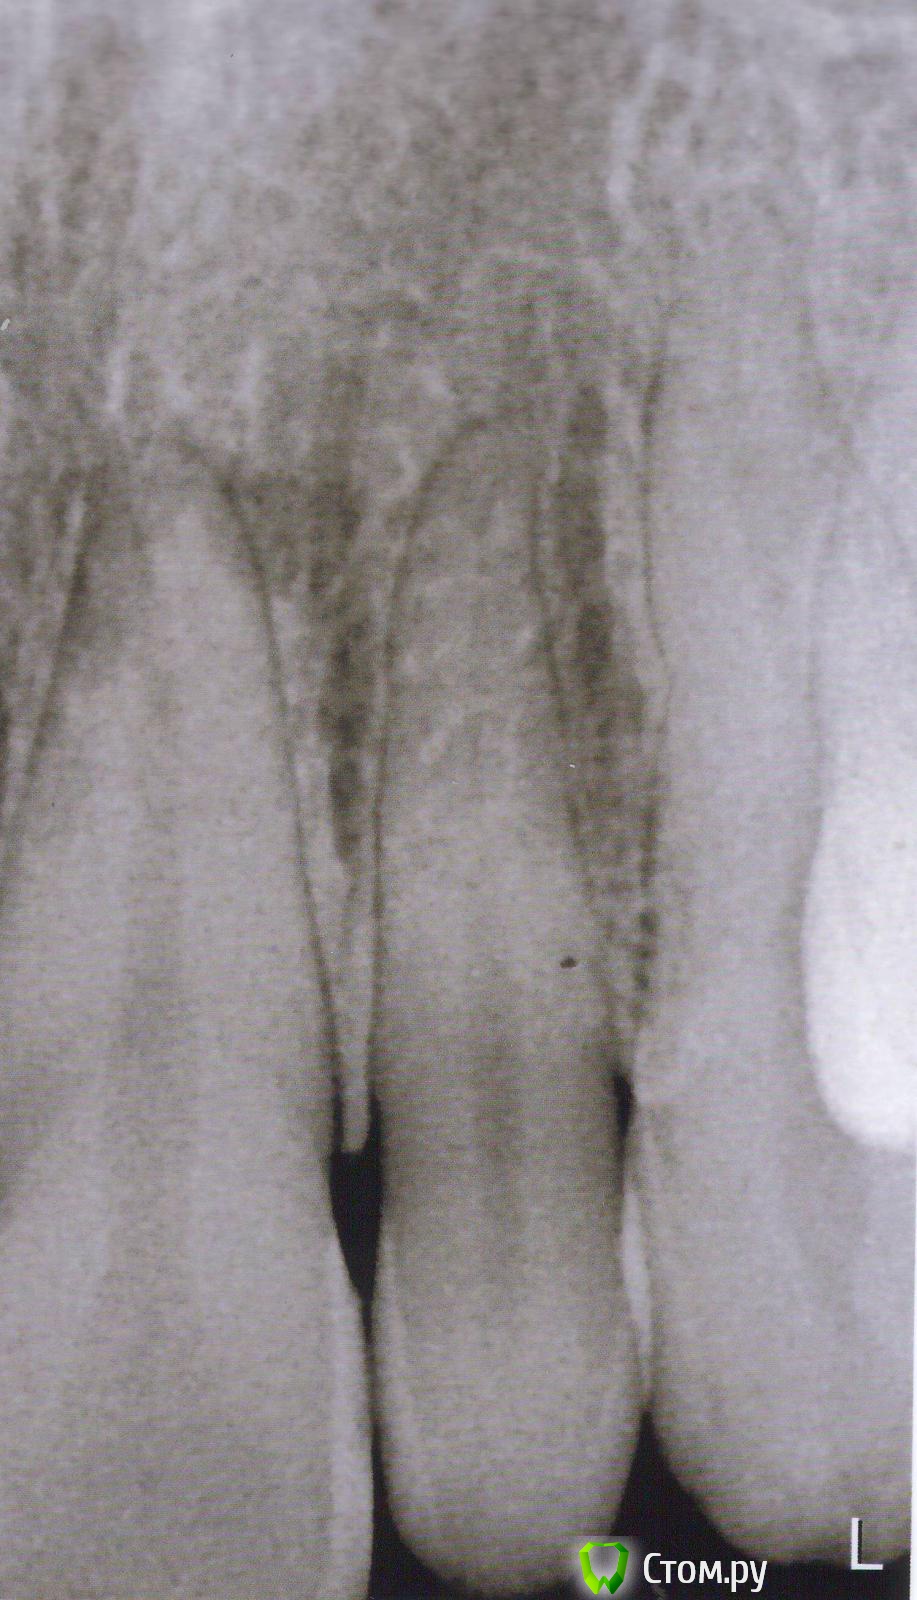

Человек Опубликовано 13 ноября, 2014 Автор Поделиться Опубликовано 13 ноября, 2014 С "22" зубом по снимку есть проблема. Сделайте прицельный снимок этого зуба. снимок К доктору попаду только на следующей неделе, то что можно проверить самостоятельно:зуб не болит, не шатается, глубоких кариозных полостей нет, в цвете не изменен, проверка льдом - зуб живой, на простукивание реакции нет, десна в цвете не изменена, при прощупывании болезненности нет Ссылка на комментарий

Гарриевич Опубликовано 13 ноября, 2014 Поделиться Опубликовано 13 ноября, 2014 Поздравляю, Отличный зуб, на ОПТГ был артефакт) Ссылка на комментарий